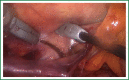

Atrial fibrillation (AF) remains the most common cardiac arrhythmia, affecting nearly 2% of the general population worldwide. Minimally invasive surgical ablation remains one of the most dynamically evolving fields of modern cardiac surgery. While there are more than a dozen issues driving this development, two seem to play the most important role: first, there is lack of evidence supporting percutaneous catheter based approach to treat patients with persistent and long-standing persistent AF. Paucity of this data offers surgical community unparalleled opportunity to challenge guidelines and change indications for surgical intervention. Large, multicenter prospective clinical studies are therefore of utmost importance, as well as honest, clear data reporting. Second, a collaborative methodology started a long-awaited debate on a Heart Team approach to AF, similar to the debate on coronary artery disease and transcatheter valves. Appropriate patient selection and tailored treatment options will most certainly result in better outcomes and patient satisfaction, coupled with appropriate use of always-limited institutional resources. The aim of this review, unlike other reviews of minimally invasive surgical ablation, is to present medical professionals with two distinctly different, approaches. The first one is purely surgical, Standalone surgical isolation of the pulmonary veins using bipolar energy source with concomitant amputation of the left atrial appendage-a method of choice in one of the most important clinical trials on AF-The Atrial Fibrillation Catheter Ablation Versus Surgical Ablation Treatment (FAST) Trial. The second one represents the most complex approach to this problem: a multidisciplinary, combined effort of a cardiac surgeon and electrophysiologist. The Convergent Procedure, which includes both endocardial and epicardial unipolar ablation bonds together minimally invasive endoscopic surgery with electroanatomical mapping, to deliver best of the two worlds. One goal remains: to help those in urgent need for everlasting relief.